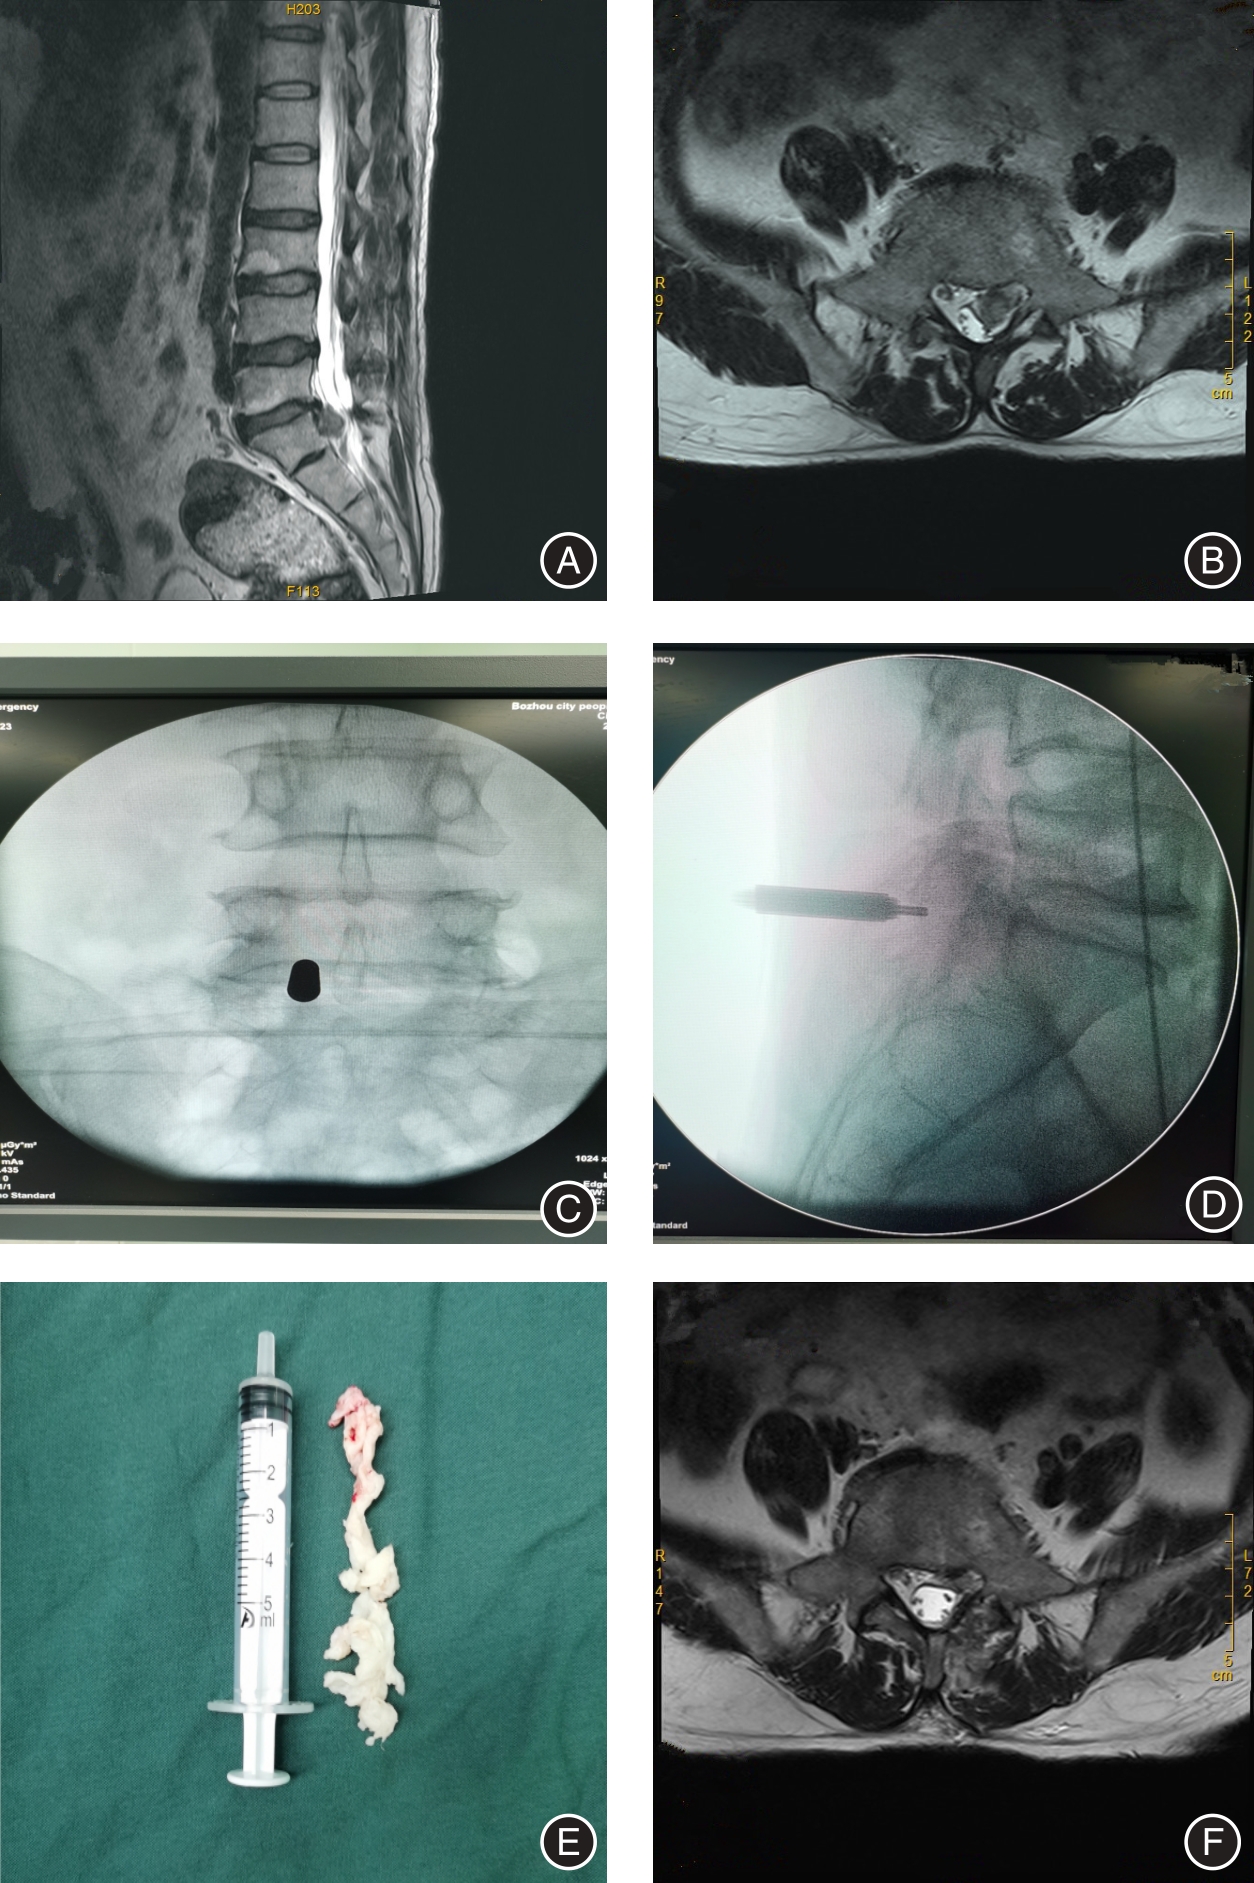

目的 分析经皮经椎间孔入路与经椎板间入路内窥镜下椎间盘切除治疗腰5/骶1椎(L5/S1)间盘突出症(LDH) 的疗效对比。 方法 采用回顾性病例对照研究,选取2020年6月至2022年12月在亳州医院脊柱外科采用经皮内窥镜手术治疗L5/S1 LDH患者62例,其中采用经椎间孔入路 32例(TELD组),采用椎板间入路 30例(IELD组)。观察指标包括术中透视次数、手术时间、住院时间、住院费用、腿痛VAS评分、ODI评分、改良MacNab疗效评价和并发症情况。 结果 62例患者均顺利完成手术和随访,无严重并发症发生。两组间在手术时间、透视次数和住院费用方面差异有统计学意义(P < 0.001),两组住院时间差异无统计学意义(P > 0.05),两组患者术后2 d、1个月及末次随访时下肢VAS评分较术前明显改善(P < 0.001)、两组患者术后2 d、1个月及末次随访时ODI评分较术前明显改善(P < 0.001),但两组间同时间点比较差异无统计学意义(P > 0.05);两组在手术优良率方面差异无统计学意义(P > 0.05),TELD组有高髂嵴患者11例均顺利完成手术。 结论 经椎间孔入路和经椎板间入路内镜手术治疗L5/S1LDH均能取得满意效果。但经椎间孔入路局部麻醉,住院费用少,伴有高髂嵴患者选择合适穿刺路径均可以顺利完成手术。经椎板间入路透视次数少,手术时间较短,但是出现硬脊膜及神经损伤风险较高,对于新手来说需要小心操作。

Objective To compare the efficacy of percutaneous transforaminal approach and translaminar approach in the treatment of L5/S1 disc herniation (LDH) under endoscopic discectomy. Methods Adopted a retrospective case-control study, and selected 62 cases of patients with L5/S1 LDH who were treated with percutaneous endoscopic surgery in the spine surgery department of our hospital from June 2020 to December 2022, and the transforaminal approach was used. (TELD) in 32 cases (TELD group), and interlaminar approach (IELD) in 30 cases (IELD group). The observation indicators included intraoperative fluoroscopy times, operation time, hospitalization days, hospitalization expenses, leg pain VAS score, ODI score, modified MacNab curative effect evaluation and complications. Results All 62 patients successfully completed the operation and follow-up, and no serious complications occurred. There were statistically significant differences in operation time, fluoroscopy times, and hospitalization expenses between the two groups (P < 0.001), but there was no significant difference in hospitalization days between the two groups (P > 0.05). The lower extremity VAS scores at the last follow-up and the last follow-up were significantly improved compared with those before operation (P < 0.001), and the ODI scores of the two groups were significantly improved at 2 days, 1 month and at the last follow-up (P < 0.001). At the same time point, there was no statistical difference (P > 0.05); there was no significant difference in the excellent and good rate of surgery between the two groups (P > 0.05). 11 patients with high iliac crest in the TELD group successfully completed the surgery. Conclusions Both the endoscopic surgery through the intervertebral foramen and the interlaminar approach can achieve satisfactory results in the treatment of L5/S1 LDH. However, local anesthesia through the intervertebral foramen approach reduces hospitalization costs, and patients with high iliac crest can successfully complete the surgery by selecting a suitable puncture path. The translaminar approach has fewer fluoroscopy times and shorter surgical time, but there is a higher risk of dura mater and nerve damage, which requires careful operation for beginners.